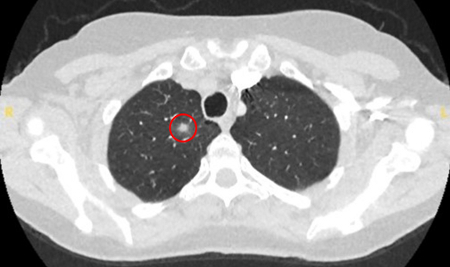

The remaining causes are infrequent and include mucoid impaction, septic emboli, arteriovenous malformations, and pulmonary amyloidosis.

[Figure caption and citation for the preceding image starts]: Computed tomography (CT) showing two areas (red circles) of mucoid impaction of the left upper lobe subsegmental bronchi, resulting in appearance that mimics a noduleFrom the collection of Dr George Tsaknis, MD, PhD, FRCP(London), MRQA, MAcadMEd, PGCert; used with permission [Citation ends].